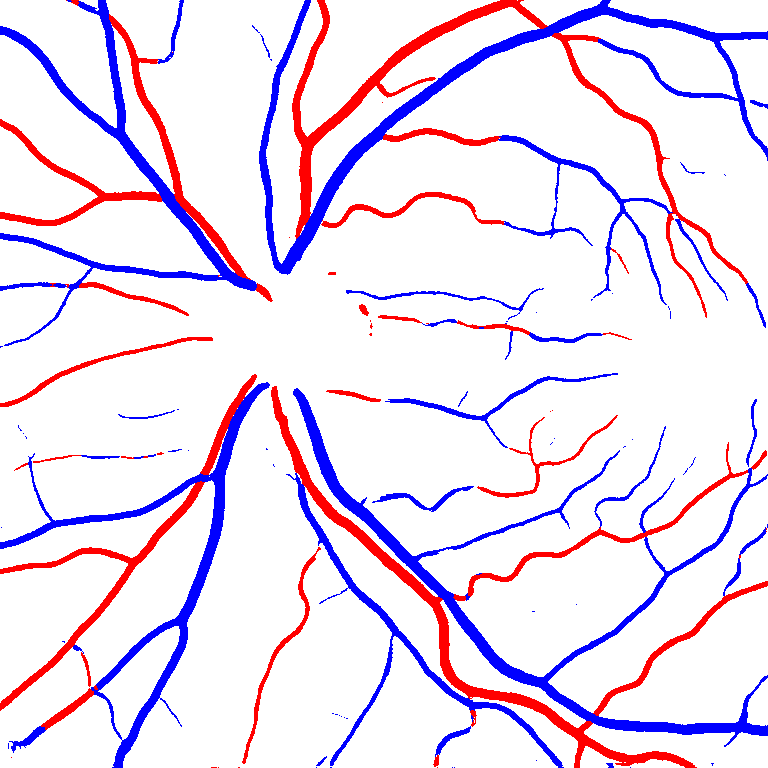

Table V presents quantitative performance benchmarks of SegRAVIR and other competing approaches for retinal artery and vein classification on the RITE dataset [11]. SegRAVIR outperforms previous state-of-the-art approaches in terms of accuracy, sensitivity, and specificity. Fig. 5 provides a qualitative comparison between segmentation outputs of SegRAVIR and the method of Hemelings et al. [40] on the RITE test set.

(a) (b) (c)